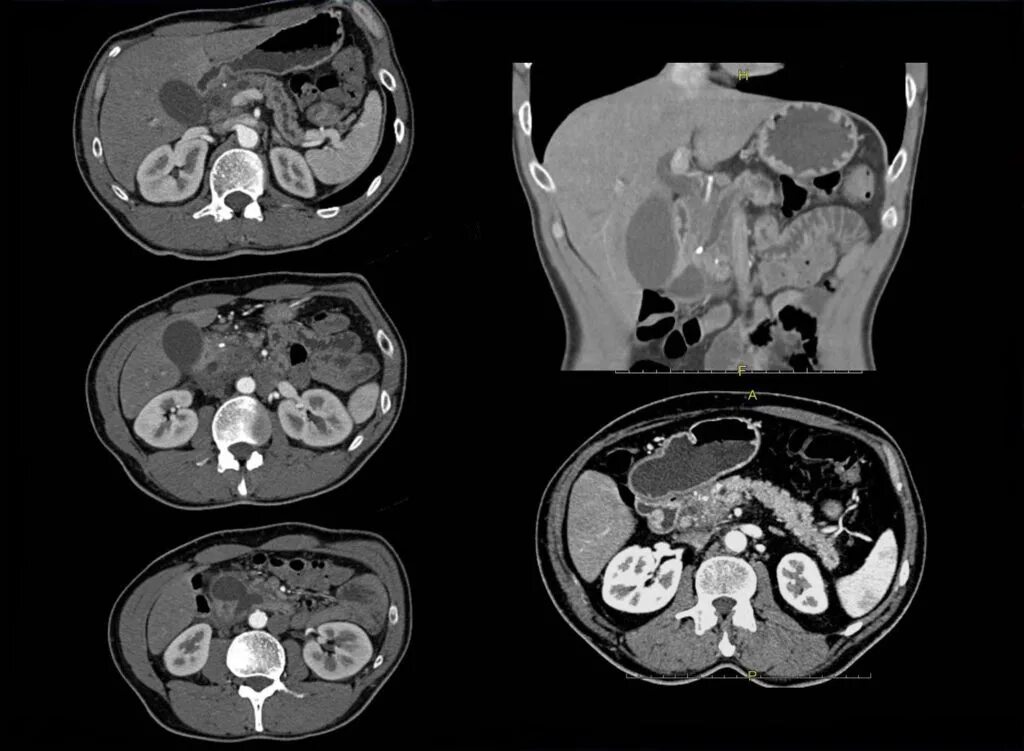

Какие виды кт